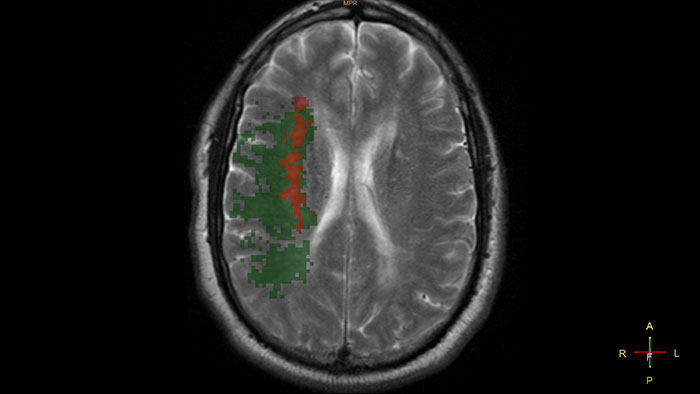

Determine areas of reduced cerebral blood flow as compared to the contralateral hemisphere

Generates qualitative and quantitative information about changes in image intensity over time. The application calculates and displays quantitative color maps of cerebral blood flow (CBF), cerebral blood volume (CBV), mean transit time (MTT) and time-to-peak (TTP), and provides summary maps which may help physicians in determining areas of reduced cerebral blood flow compared to the contra lateral hemisphere.

Reviewing brain tissue perfusion viability

Provides physicians with supporting information for the evaluation of stroke, or assessment and follow-up of brain tumors. The application supports the analysis of T2* Perfusion studies to generate parametric data including TTP, MTT or Tmax.